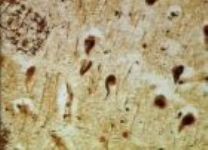

Neurotrasmettitori

Due fili elettrici, per contribuire a costruire un circuito, si aggiuntano con un pò di nastro isolante. Le fibre nervose si "aggiuntano e comunicano con sostanze chimiche, chiamate "neurostrasmettitori".

Nel corpo umano sono conosciuti più di 400 neurotrasmettitori.